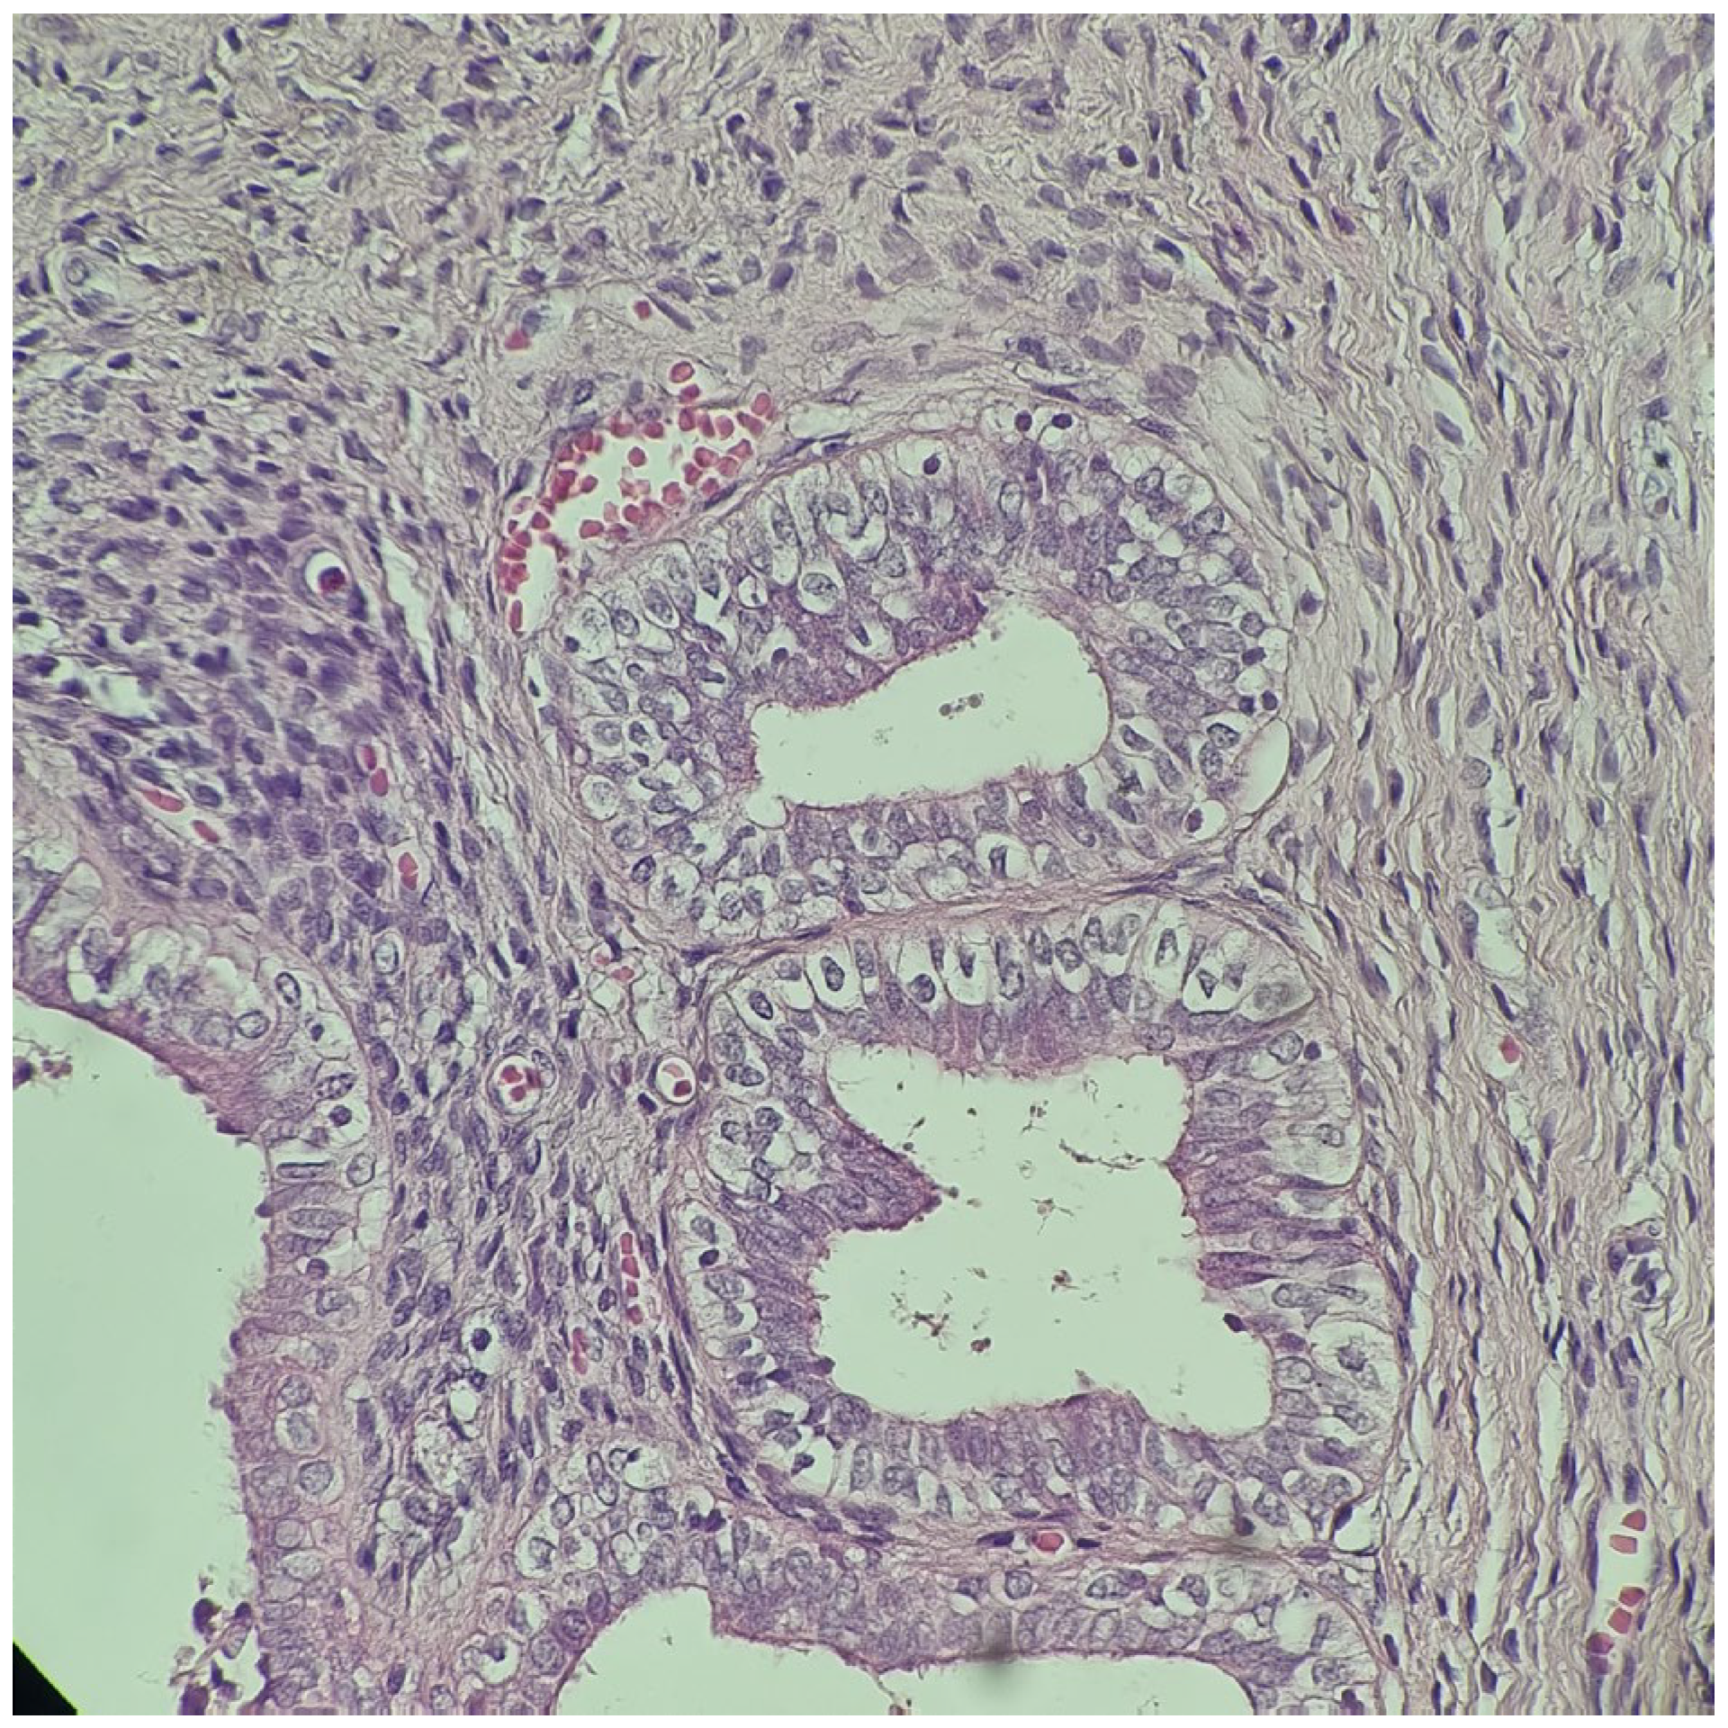

2.4. At Age 13 Years